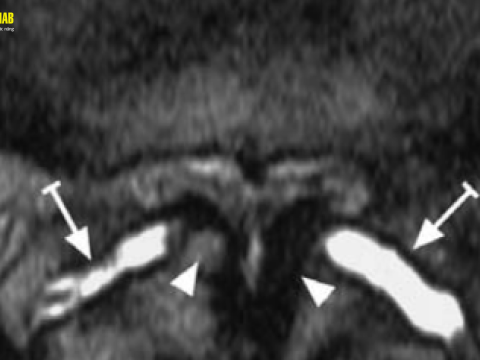

Tiêm cột sống